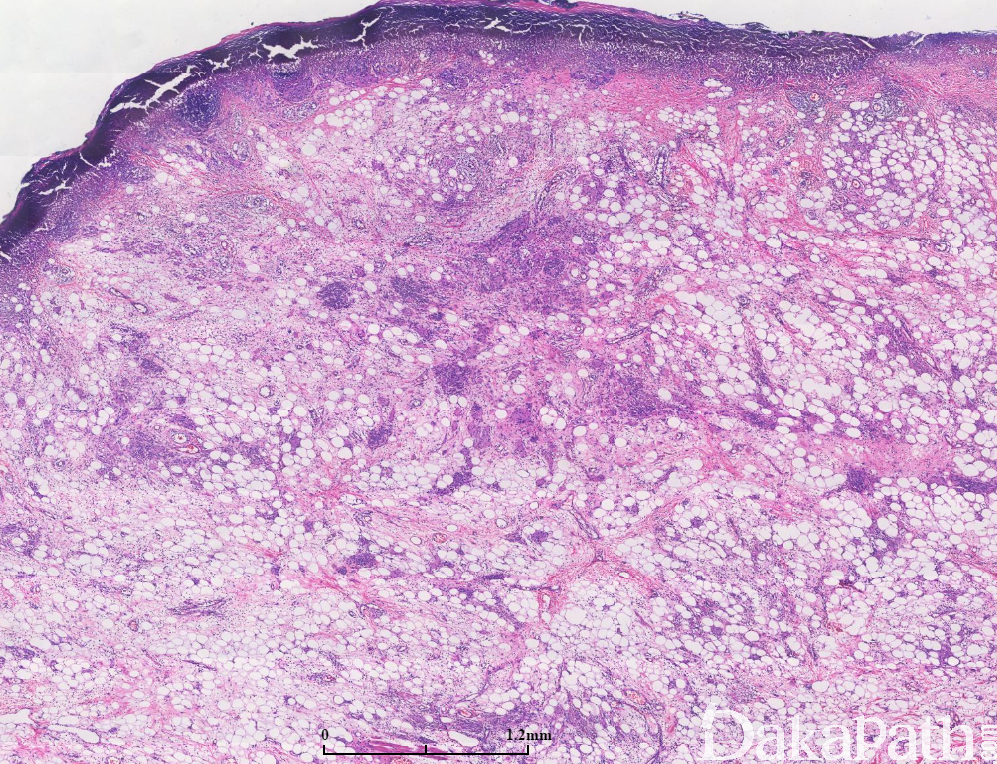

脂肪瘤样皮内痣

先天性黑色素痣具有多向分化的潜能,包括神经纤维、雪旺细胞、不成熟横纹肌,以及脂肪细胞。有人认为反复创伤病变可以促使这种分化。神经纤维瘤与黑色素瘤都源于神经嵴细胞,所以也具有多向分化功能,单从形态学上与神经分化的黑痣有时相似,特别是表皮溃损时不能找到皮内黑色素痣成份,且伴有脂肪分化的黑色素瘤多为皮内痣。

表皮下见病变大部分由成熟脂肪细胞构成,大致对称,主要累及真皮,脂肪细胞混杂有散在的梭型细胞,气球样细胞,近表皮处可见成团排列的细胞,个别细胞核增大,胞浆空泡状,偶见多核细胞,病变近底部处可见触觉小体样结构。无片状坏死,未见核分裂象。皮肤表皮可有破溃。

S100. HMB45. SOX10 阳性,且从浅到深阳性强度逐渐减弱,Ki-67 指数低。